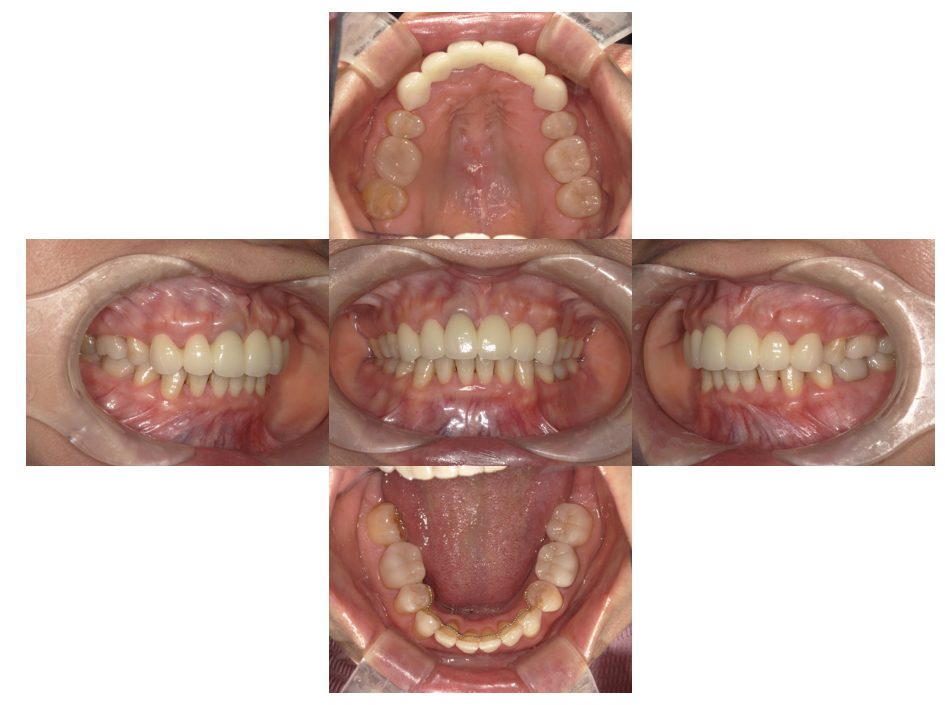

矯正治療・インプラント治療・セラミック治療・金属床(部分入れ歯)の症例紹介(三隅歯科クリニック)

三隅 賢祐(三隅歯科クリニック)

症例詳細

| 主訴 | 50代女性 以前いれた入れ歯が合わなくて使っていないので、しっかり噛めるようになりたい |

| 治療内容 | 矯正治療、インプラント治療、セラミック治療、金属床(部分入れ歯)を行いました。 |

| 治療費 | 4,200,000円(税込み) |

| 治療期間 | 2年(矯正治療期間 1年) |

| 治療回数 | 50回 |

| 想定されたリスク | 重度の歯周病で臼歯部の歯槽骨がかなり吸収していたため、インプラントが脱落するリスクがありました。 |